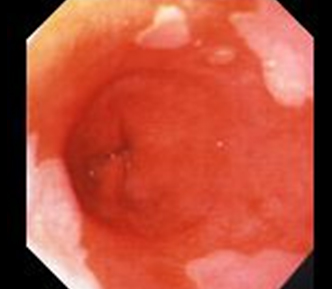

Ο οισοφάγος Barrett είναι μια παθολογική κατάσταση που αφορά το κατώτερο τμήμα του οισοφάγου. Οφείλει το όνομά του στον γιατρό Norman Barrett ο οποίος αρχικά περιέγραψε την νόσο(φωτο).

Οισοφαγογαστροσκόπηση: Η αλλαγή στο χρώμα της εσωτερικής επικάλυψης του κατώτερου οισοφάγου στην ενδοσκόπηση από απαλό λευκωπό ρόζ όπως φαίνεται φυσιολογικά σε έντονοτερο ροζ χρώμα (του σολωμού) εγείρει σοβαρές υποψίες ότι έχει αναπτυχθεί οισοφάγος Barrett. Συνήθως το εντονότερο αυτό χρώμα εμφανίζεται με την μορφή γλωσσοειδών προσεκβολών ή νησιδίων μέσα στο φυσιολογικό λευκωπό ροζ και αντιστοιχεί στο μεταπλαστικό επιθήλιο του οισοφάγου Barett.